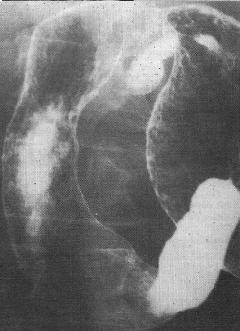

Complication perfore une

ulcer gastroduodenal est image de croissance gasseuse

sous diapragmatique droit . Cliche de face AP |